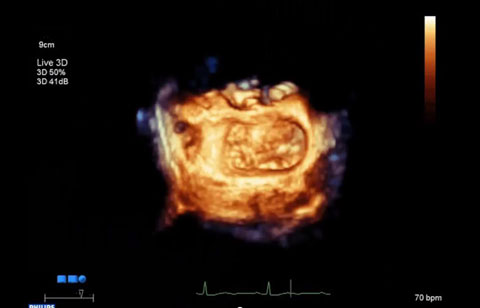

بعد تشخيص مريض بارتجاع الصمام الميترالي، ما هي خيارات العلاج المتوفرة له؟ إذا لم يكن مرشحًا للخضوع لعملية القلب المفتوح، يمكنك التفكير في معالجته عبر إصلاح الصمام الميترالي باستخدام القسطرة (TMVR). وفي يومنا الحالي، تؤمن حلول التصوير المبتكرة والأجهزة المتوفرة حديثًا خيارات جديدة لبعض المرضى.